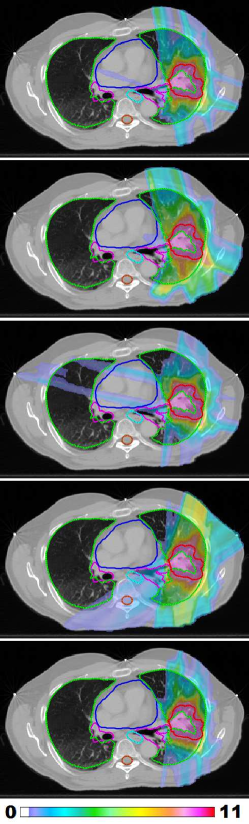

Figure 1: LABEL:sub@prt_allFracs and LABEL:sub@lng_allFracs Fraction-variant treatment plans for each of five fractions for cases “PRT” and “LNG”. The PTV receives a uniform dose of 888 Gy (approximately) at each fraction for case “PRT” and 9.6 Gy (approximately) for case “LNG”. LABEL:sub@hnk_allFracs Dose colormaps for fractions 1, 7, 13, 19, and 25 for case “H&N”. The PTV receives a uniform dose of 2.2 Gy (approximately) throughout the treatment course.

Figure 1LABEL:sub@lng_allFracs shows dose colormaps for each of the five fractions for the FV lung plan. Despite the variation in dose distributions, the PTV is covered uniformly at each fraction. Each voxel in the PTV receives a dose of approximately 48/5=9.64859.648/5=9.6 Gy per fraction. Figure 5 shows the beam angles that were selected for each of five fractions for the lung case using the FV BOO algorithm. On average, only 6.6 beams per fraction were selected. Again, the algorithm did not select the same set of beam angles for any two fractions. A total of 27 distinct beam firing positions were utilized, as visualized in figure 5LABEL:sub@lng_beams_allFracs.

Figure 6 shows the total dose distribution, summed over all five fractions, for the FV plan (top row) as well as a conventional 7-beam FI plan (middle row) and a conventional 13-beam FI plan (bottom row). Corresponding dose-volume histograms, comparing the FV plan with the two FI plans, are shown in figure 7. Compared with the 7-beam FI plan, the FV plan achieves dosimetric improvements for the proximal bronchus and the normal left lung. Mean dose was reduced by 1.9 Gy for the normal left lung, while max dose was reduced by 6.0 Gy for the proximal bronchus and by 2.0 Gy for the normal left lung. The R50subscript𝑅50R_{50} values are 2.98 for the FV plan, 4.12 for the 7-beam FI plan, and 3.25 for the 13-beam FI plan. This substantial improvement in dose compactness for the FV plan can be visually appreciated in figure 6. The dosimetric quality of the FV plan is similar to that of the 13-beam FI plan, while using only half as many beams per fraction.

Figure 6: The dose distribution (summed over all five fractions) for FV plan with average of 6.6 beams per fraction (top row) as well as a 7-beam FI plan (middle row) and a 13-beam FI plan (bottom row). Dose below 5 Gy is not shown.